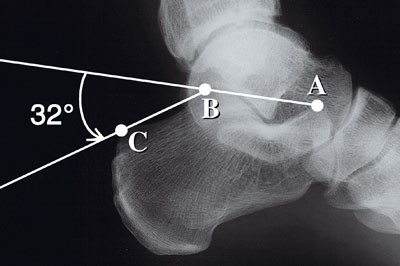

L'angle de Bohler du calcaneum est un angle radiologique formé par 2 lignes, l'une antérieure passant par par le sommet de la surface talienne postérieure (thalamus de Destot) et le bbord supérieur de la grosse tubérosité, l'autre postérieure passant par le sommet de la surface talienne postérieure et le bord supérieur de la grande apophyse, cet angle est un angle important en traumatologie PARCEQU'il s'ouvre lors des enfoncements du thalamus dans le calcannéum.

L'angle de Boher du calcaneum mesure 90° CAR il est formé par l'intersection de 2 droites, l'une passant par le bord supérieur et l'autre passant par le bord inférieur de l'os.